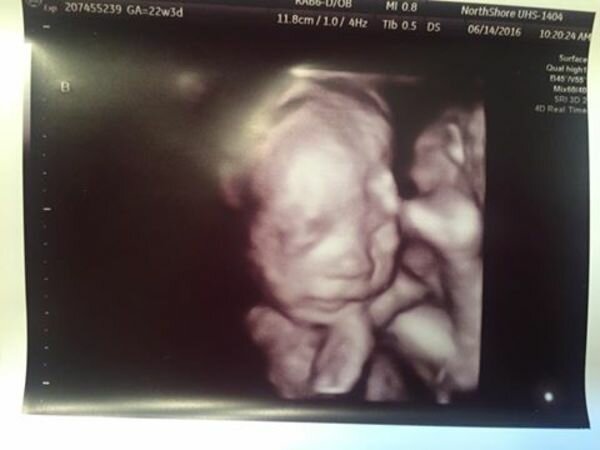

Byla připravena na to nejhorší. Pak ale uslyšela zprávy, které jí zase obrátily život vzhůru nohama. Během ultrazvuku si doktor všiml dvou chlapců a jedné dívky. Courtney se chystala porodit trojčata!

Obrázek z google.com

- „Jsem úplně beze slov. Ale byla jsem ráda, že mám další tři úsměvy, které by mi Briana připomněly, “řekla Courtney v rozhovoru.